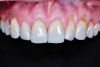

Envelope flaps,15 which are one of the most common flap designs, have the advantage of simplicity, blood supply, sulcular access to the roots to address NCCLs or for root preparation, and predictable root coverage (Figure 1). Because this flap design involves reflection of the papillae, it may affect papillary height upon healing. Envelope flaps may be utilized with vertical releasing incisions as a variation.

(1.) Example of an envelope flap, which offers the advantages of simplicity, blood supply, sulcular access to the roots to address NCCLs or for root preparation, and predictable root coverage.

Figure 1